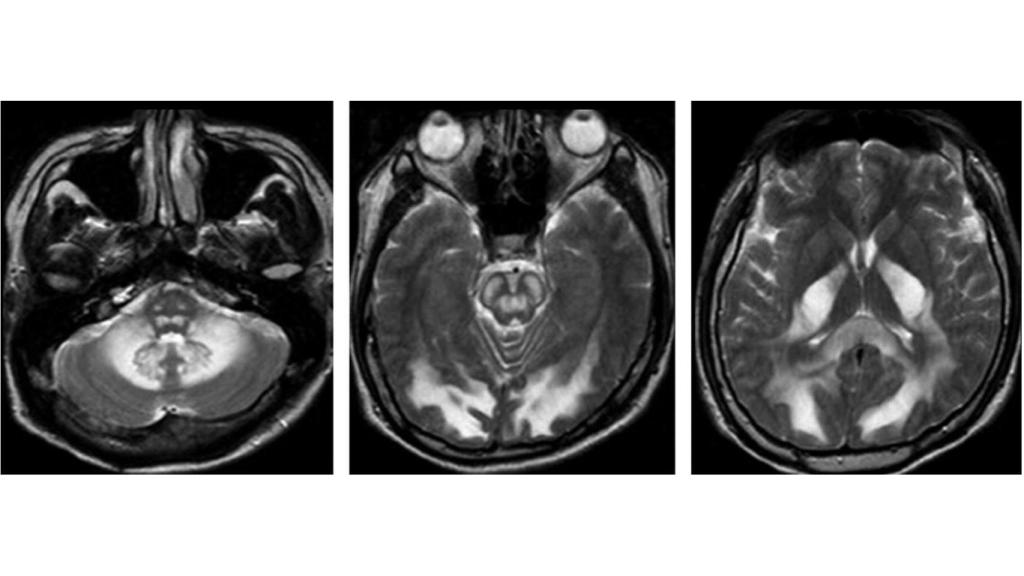

Diferencias en densidad de materia gris (coloreada) en consumidores de nicotina. Researchgate.net